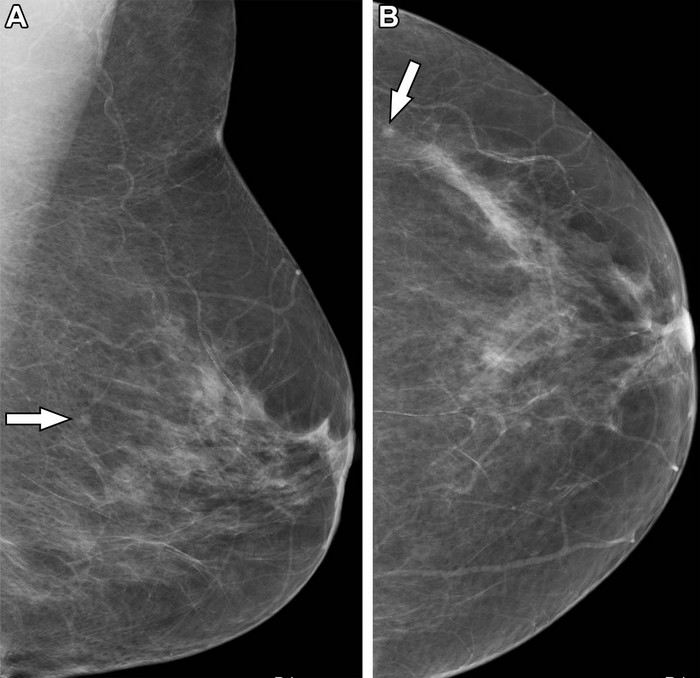

IMAGE: MAMMOGRAMS IN A 50-YEAR-OLD WOMAN UNDERGOING HER FIRST SCREENING MAMMOGRAPHIC EXAMINATION. A 3-MM MASS (ARROW) IS DEMONSTRATED IN THE LEFT BREAST ON THE (A) MEDIOLATERAL OBLIQUE AND THE (B) CRANIOCAUDAL VIEW. IT WAS NOT RECALLED BY THE RADIOLOGIST WHO READ THE MAMMOGRAM FIRST BUT WAS RECALLED BY THE RADIOGRAPHER WHO READ THE IMAGE SECOND. BECAUSE THE OPINIONS WERE DISCORDANT, THE CASE WAS RECALLED FOR FURTHER ASSESSMENT AFTER ARBITRATION BY A THIRD READER. US-GUIDED BIOPSY DEMONSTRATED A 3-MM HISTOLOGIC GRADE 1 DUCTAL CARCINOMA. view more